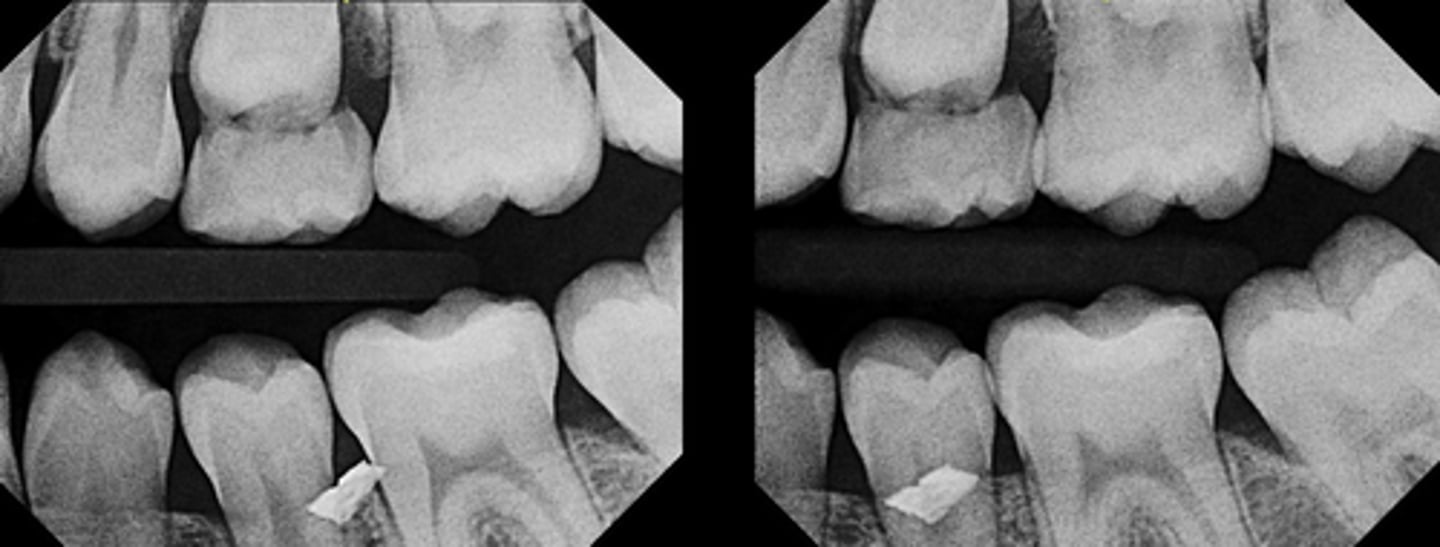

Two periapical radiographs are obtained:

- The first radiograph is taken with normal horizontal angulation.

- The second radiograph is taken with a distal horizontal tube shift.

On the second image, the suspected canal appears to move distally, in the same direction as the tube shift.

Based on these findings, where is the suspected canal most likely located?

B. Lingual (palatal) to the main mesiobuccal canal